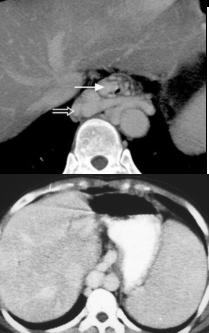

Hernie hiatale de type

I en coupe axiale TDM , fenetre mediastinale .

La poche hydro-aerique gastrique glisse alongee au

dessus hiatus oesophagien en arriere aureillete

gauche et ventricule gauche . |

Meme cas en coupe frontale (

coronale ) .Le cardia et une partie de estoma

situent au dessus le diapragme . Image du

coupe est si nette |